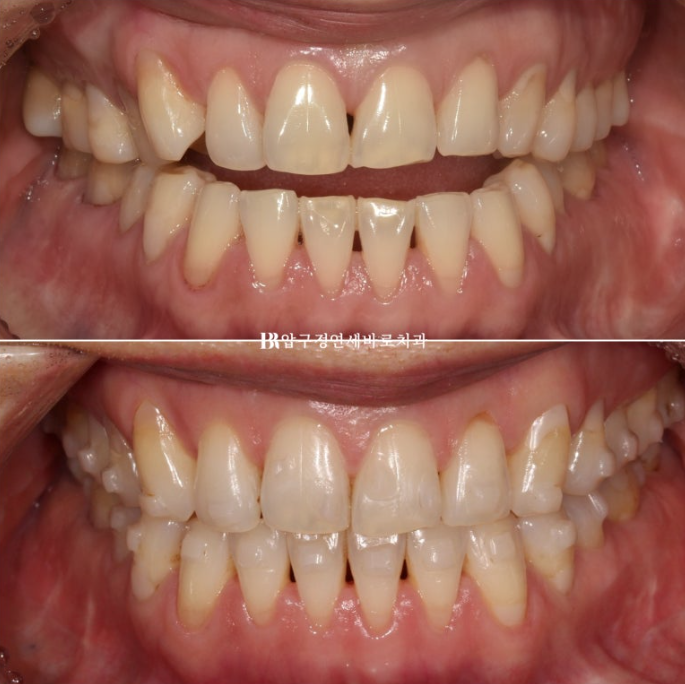

23.05~23.12

앞니가 떠 있는 개방교합에서

첫번째 작은어금니까지 8개 치아는 떠있고 두번째 작은어금니부터 큰어금니까지 3개씩 닿아있는 상태입니다.

이런 상태에서는 닿고있는 위 어금니 3개씩 총 6개 치아를 함입시키는 치료계획으로 진행합니다.

7개월에 걸쳐 1차세트 마무리 후 추가장치를 이해 리파인먼트 재제작에 들어갔습니다.

걱정하시는 교합도 잘 마무리 되었습니다.